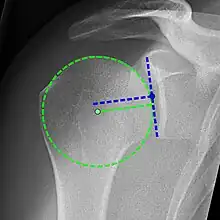

X-ray projectional radiography cannot directly reveal tears of the rotator cuff, a 'soft tissue', and consequently, normal X-rays cannot exclude a damaged cuff. However, indirect evidence of pathology may be seen in instances where one or more of the tendons have undergone degenerative calcification (calcific tendinitis). The humeral head may migrate upwards (high-riding humeral head) secondary to tears of the infraspinatus, or combined tears of the supraspinatus and infraspinatus.[47] The migration can be measured by the distance between:

- A line crossing the center of a line between the superior and inferior rims of the glenoid articular surface (blue in image).

- The center of a "best-fit" circle positioned over the humeral articular surface (green in image)

Normally, the former is positioned inferiorly to the latter, and a reversal is therefore indicating a rotator cuff tear.[47] Prolonged contact between a high-riding humeral head and the acromion above it, may lead to X-rays findings of wear on the humeral head and acromion and secondary degenerative arthritis of the glenohumeral joint (the ball and socket joint of the shoulder), called cuff arthropathy, may follow.[46] Incidental X-ray findings of bone spurs at the adjacent acromioclavicular joint may show a bone spur growing from the outer edge of the clavicle downwards towards the rotator cuff. Spurs may also be seen on the underside of the acromion, once thought to cause direct fraying of the rotator cuff from contact friction, a concept currently regarded as controversial.